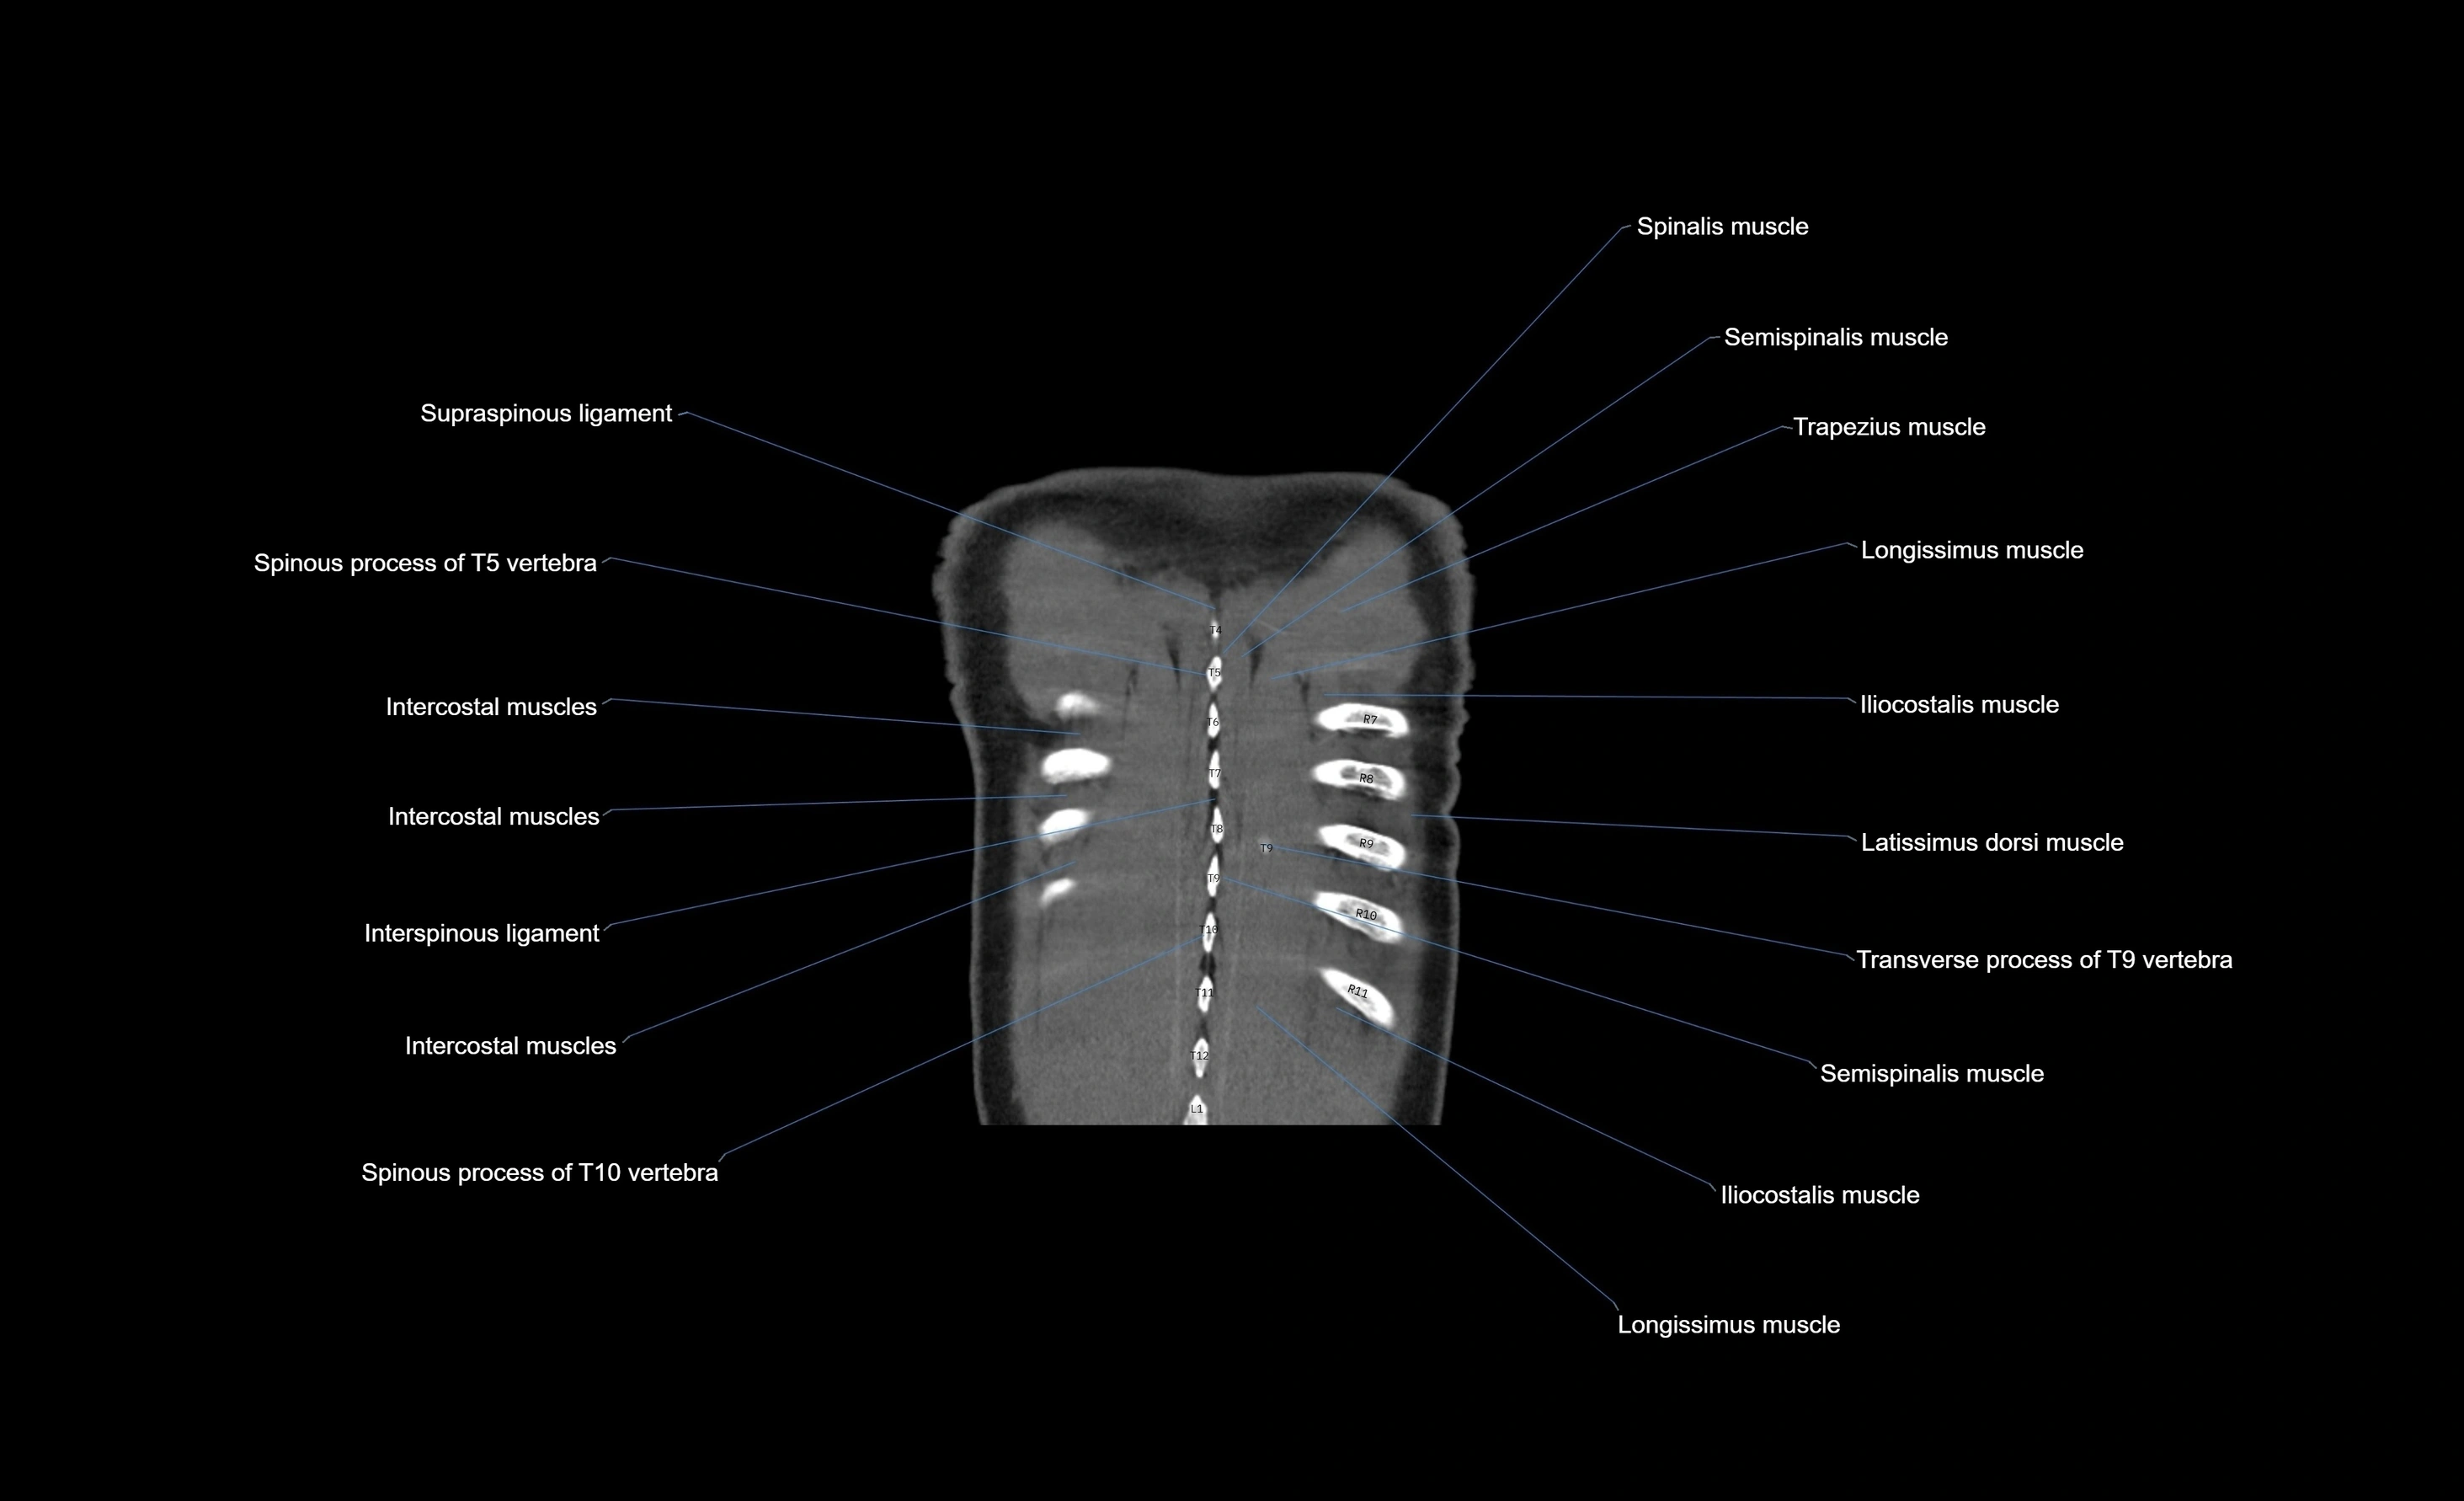

- Intercostal muscles

- Interspinous ligament

- Spinous process of vertebra

- Trapezius muscle